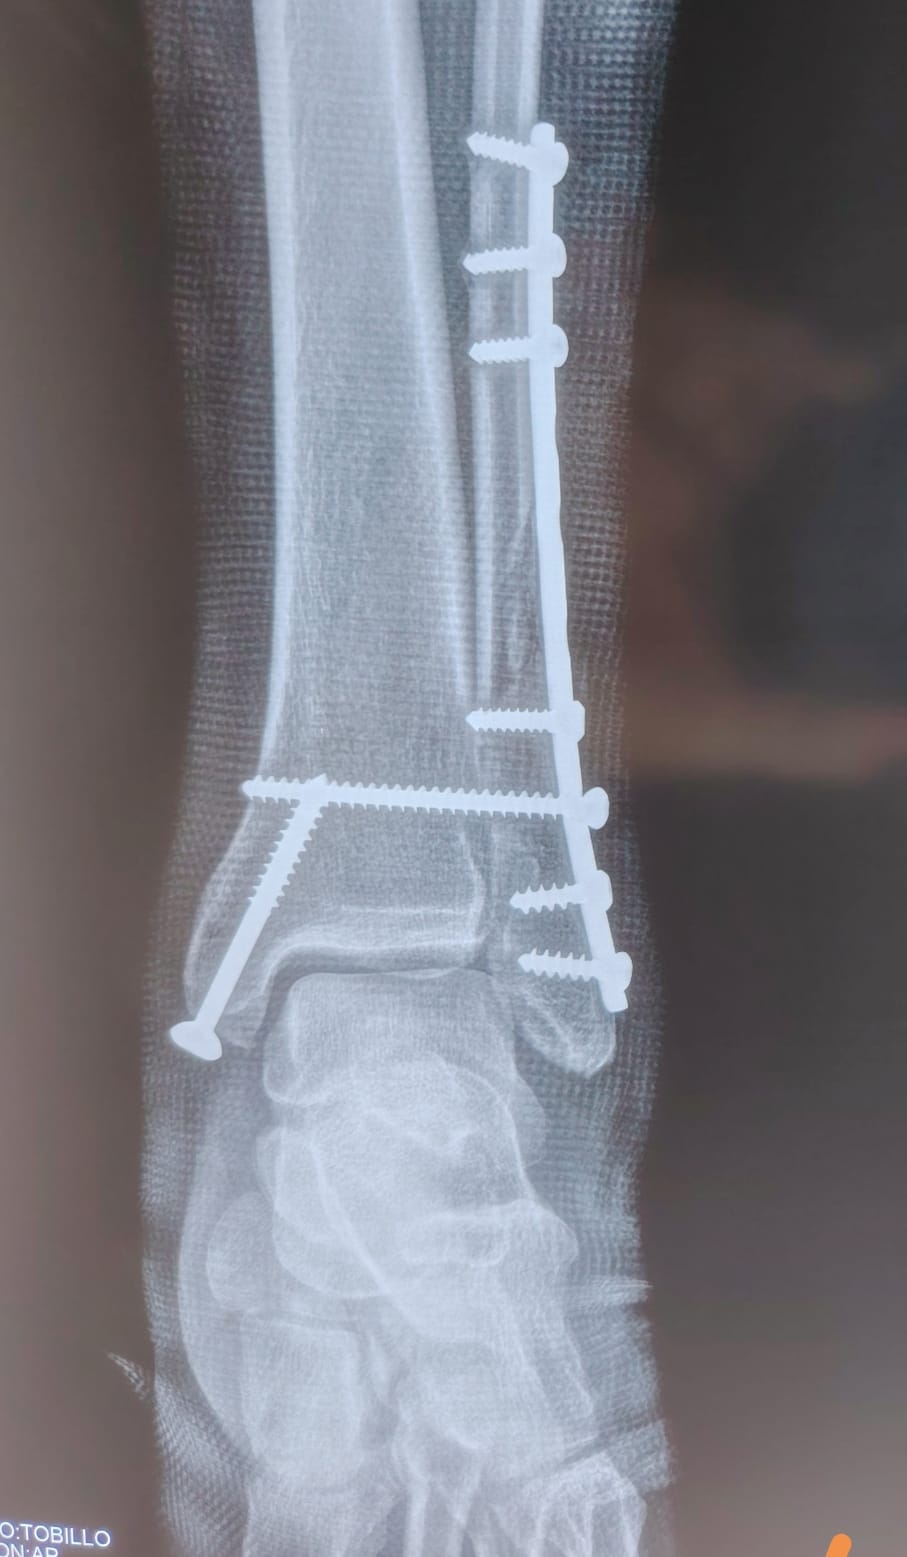

Imagen de fractura de tobillo post - operada